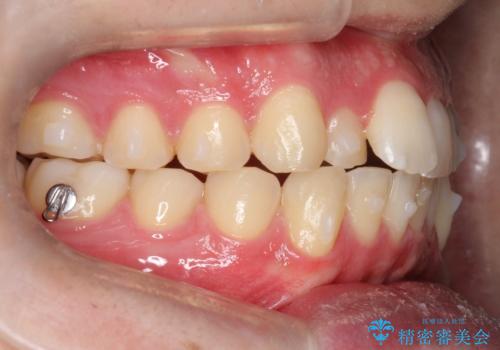

- 前歯の歯並びの改善を希望され来院された患者様です。

初診時の歯並びの状態としては、上下ともに前歯部の中等度以上のがたつき(叢生)があり、右の前歯が1本飛び出した状態でした。

抜歯は行わず上下顎ともに、主に歯列弓の拡大とディスキング(歯と歯の間に隙間を作る処置)を行い叢生を改善しました。

矯正装置としてはマウスピースを使用しています。